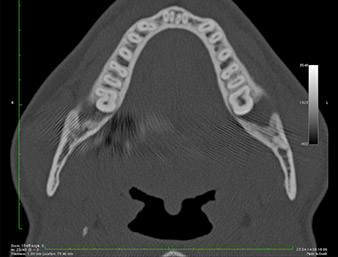

In der 3D-Aufnahme (digitales Volumentomogramm) war ersichtlich, dass sich der Wurzelrest weit disto-kaudal im Übergang vom horizontalen zum aufsteigenden Anteil des Unterkiefers befand (Abb. 2).

Unser Patient besaß anamnestisch gute Voraussetzungen (Nichtraucher, 26 Jahre) für einen erfolgreichen Eingriff. Wegen des Hinweises auf enge Lagebeziehung des Wurzelrestes zum N. alveolaris inferior in der Panoramaschicht-Aufnahme wurde zusätzlich eine digitale Volumentomografie erstellt (6).